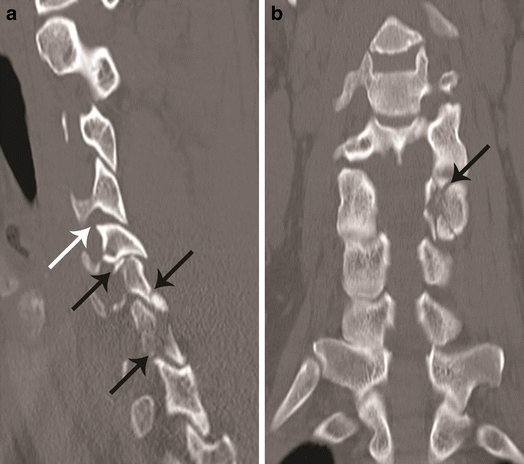

Hyperextension compression injury. a Parasagittal CT image shows C6, C7 articular pillar and process comminuted fracture with vertical orientation (black arrows). Focal anterior widening of C4–C5 facet joint (white arrow) is a characteristic feature of hyperextension injury. b Coronal CT image from the articular pillar in a different patient shows left C5 articular pillar fracture with vertical orientation and comminution (black arrow)

Hyperextension compression with traumatic spondylolisthesis. a Mid-sagittal CT image shows anterior listhesis of C7 over D1 (white arrow). This could result from hyperflexion distraction or, rarely, hyperextension injury. The spinolaminar line is continuous at the level of anterior translation, which suggests a hyperextension injury vector. b Left parasagittal image from the facet joint shows a vertically oriented fracture through the left pars interarticularis of C7 (black arrow) with impaction of the tip of the inferior articular process of C6 in the fracture gap—highly suggestive of hyperextension injury. Similar pars interarticularis fracture was also seen on the right side of C7 (not shown)